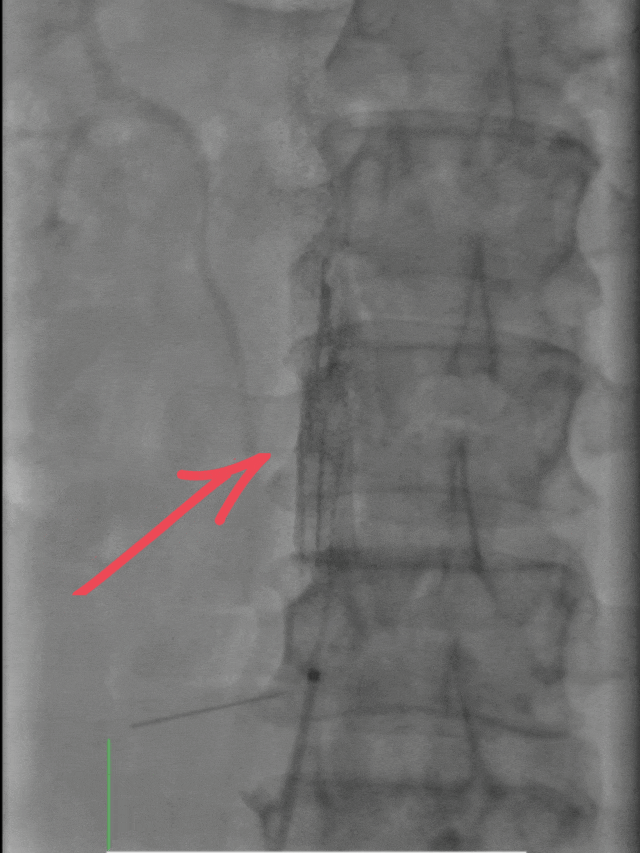

✅首先通过下肢静脉造影,清晰定位血栓位置与负荷;

✅随后置入下腔静脉滤器,如同在血管内筑起“防护网”,有效预防血栓脱落引发更严重的肺栓塞;

✅最后通过肺动脉造影,精准实施取栓、碎栓操作。

整个手术仅用一个半小时便顺利完成,血栓被彻底清除。术后效果立竿见影,小李的胸闷、憋气症状明显缓解,咳嗽咳痰好转,右下肢疼痛也有所减轻。